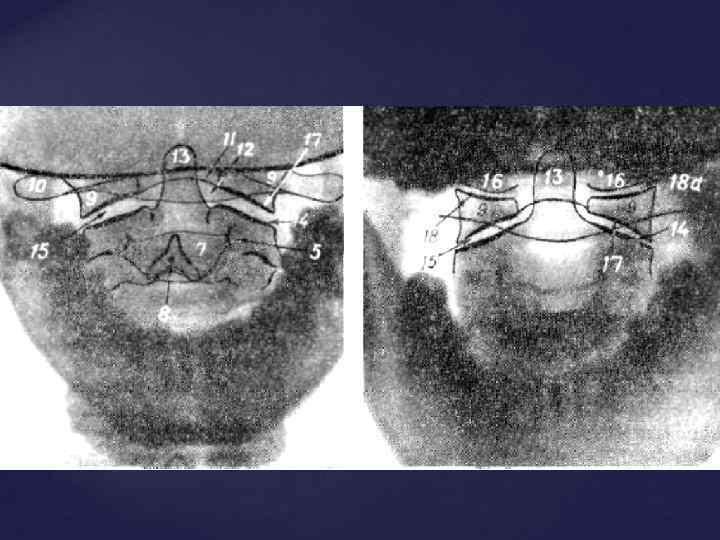

СРОКИ ОКОСТЕНЕНИЯ КОСТЕЙ ЧЕЛОВЕКА 1. ПОЗВОНОЧНИК - появление трех точек окостенения (т. о. ) (тело и две половины дуги) - внутриутробно - синостоз дуги и тела – 2 -3 года - синостоз обеих половин дуг – 1 -8 лет (в зависимости от уровня) - появление добавочных т. о. (апофизы - лимбы позвонков) – 7 -8 лет - полное слияние всех добавочных т. о. - 23 -26 лет - синостозирование крестца – 11 -12 лет

СРОКИ ОКОСТЕНЕНИЯ КОСТЕЙ ЧЕЛОВЕКА 1. ПОЗВОНОЧНИК - появление трех точек окостенения (т. о. ) (тело и две половины дуги) - внутриутробно - синостоз дуги и тела – 2 -3 года - синостоз обеих половин дуг – 1 -8 лет (в зависимости от уровня) - появление добавочных т. о. (апофизы - лимбы позвонков) – 7 -8 лет - полное слияние всех добавочных т. о. - 23 -26 лет - синостозирование крестца – 11 -12 лет